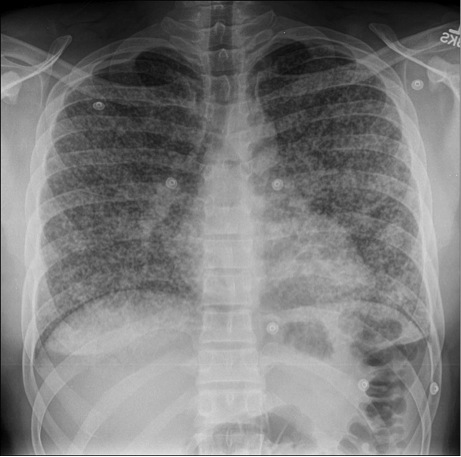

Figure 2: Computed Tomography (CT) of the chest demonstrated diffuse micro-nodular infiltrates throughout both lung fields without associated lymphadenopathy